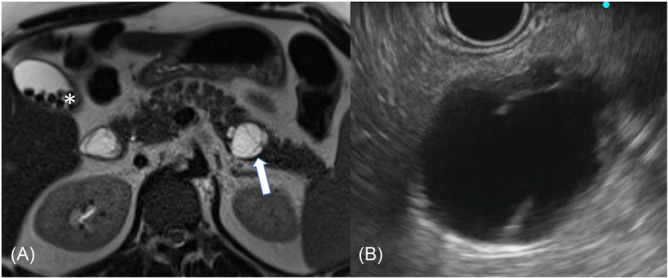

Pancreatic mucinous cystic neoplasms (MCNs) are rare tumors predominantly identified in middle-aged females. Occurrences are extremely rare in children. We report a rare case of pancreatic MCN in an adolescent. A 14-year-old female with Smith-Magenis syndrome and steatotic liver disease (SLD) presented with abdominal discomfort. Magnetic resonance elastography obtained for SLD revealed cholelithiasis and a 0.5-cm cyst in the distal pancreas. Observation was recommended by her pediatric surgery provider. At 18 years old, contrast-enhanced abdominal magnetic resonance imaging showed a 2.4-cm mildly complex, septate, cystic lesion along the distal pancreas with no soft tissue component, pancreatic atrophy, or ductal dilation. Endoscopic ultrasound with cyst fluid cytology showed no definitive neoplasm. Carcinoembryonic antigen level of cyst fluid was markedly elevated at 11,207 ng/mL, concerning an MCN. She was referred to Hepatopancreatobiliary Surgery for evaluation and underwent robotic-assisted distal pancreatectomy. Final pathology revealed a 2.8-cm low-grade MCN with intermediate-grade dysplasia.